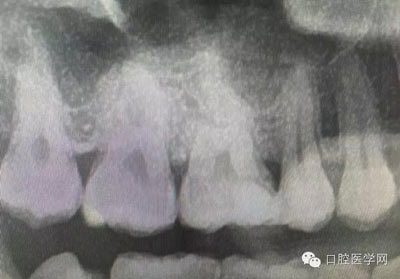

根管再治療是我們比較頭疼的,尤其是那些冠修復過的,我們有很多的麻煩需要去溝通,比如可能導致的側(cè)穿、可能沒有看到的腐質(zhì)、可能導致的崩瓷,或者是后期可能出現(xiàn)冠折......這些需要我們和患者好好的溝通。全瓷冠還好些,金屬冠根測的時候很是麻煩,總之我們做修復的時候不要單純的追求速度,追求效益,適當?shù)淖⒁庀挛覀兊幕A(chǔ)治療和設(shè)計。

深齲或者是齲壞備洞的時候意外穿髓,我們怎么處理好些?后期出現(xiàn)的牙髓的癥狀,是我們操作的問題?比如細菌層的存在,我們沒有清理干凈?還是我們窩洞沒有進行消毒,或者是隔濕沒有做好導致的粘結(jié)出現(xiàn)問題,還是材料充填的時手法不對,導致的材料收縮過大,還是我們的光照設(shè)備出現(xiàn)了老化沒有完全達到想要的固化,還是懸空的釉質(zhì)沒有去除導致的微滲漏的發(fā)生,或者是材料本身對牙髓產(chǎn)生的刺激,還是材料選擇的問題,或者是我們對材料的性能和說明沒有足夠的了解導致的,沒有按照材料的要求去做,還是我們自身對牙齒情況的判斷出現(xiàn)的問題......